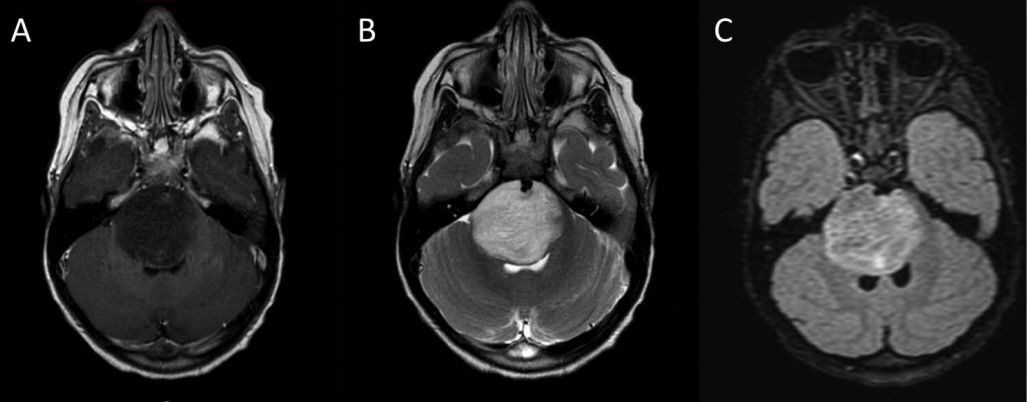

男性18岁,发热、恶心、呕吐3天。(补充:自行口服甲硝唑1.2g/d 后出现共济失调、眩晕。)

答案: 甲硝唑相关脑病(Metronidazole-induced encephalopathy MIE)。

本周一的晨读病例都是良心病例,难度程度均不高。特征性影像表现剑指甲硝唑和山豆根。甲硝唑的神经毒性主要包括前庭小脑系统损害、自主神经损害、视神经损害、周围神经损害及癫痫发作等。甲硝唑引起的CNS损害多具有可逆性,及时停药后,临床症状可短期内改善。MIE的MRI改变:典型病变区域在小脑齿状核、中脑、脑桥被盖、延髓背侧及胼胝体压部,通常双侧对称受累。小脑齿状核和中脑下丘对称性病灶被认为是MIE的特征性表现。MIE鉴别诊断:中枢神经系统脱髓鞘疾病及其他代谢性和中毒性脑病。其中,Wernicke脑病最需与MIE鉴别。WE特征MRI表现:第三、四脑室旁、导水管周围、乳头体、四叠体、丘脑对称性病灶。